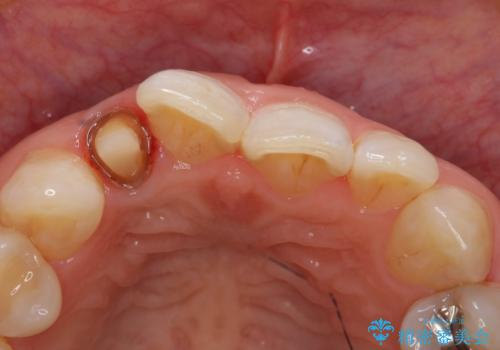

- 右上2番目の歯の変色が気になるといらっしゃった方の症例です。

再根管治療終了後、オールセラミッククラウンによる補綴を行いました。